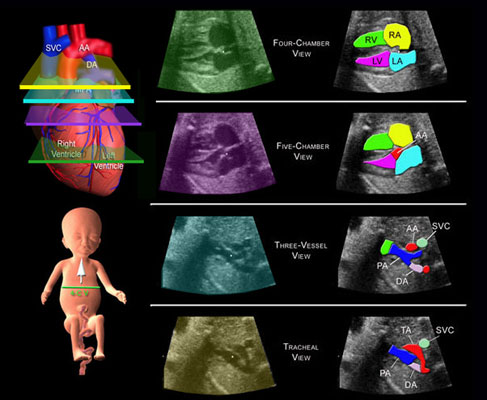

The following images illustrate the four different levels used to identify cardiac anatomy using the Sweep Technique.

Four-Chamber View

This illustrates the level that the four-chamber view is imaged

(green). The main pulmonary artery (MPA) and the aorta (AA)

are not imaged at this level. SVC=superior vena cava, DA=ductus

arteriosus, RV=right ventricle, RA=right atrium, LV=left ventricle,

LA=left atrium.

Five-Chamber View

This is the level of the five-chamber view and illustrates the

aorta (AA) exiting the left ventricle. RV=right ventricle, RA=right

atrium, LV=left ventricle, LA=left atrium.

3-vessel View

This is the 3-vessel view because 3 vessels are observed; the

superior vena cava (SVC), the cross-section of the ascending

aorta (AA), and the full length of the main pulmonary artery

(PA). This is an important view because it illustrates the ascending

aorta perpendicular to the main pulmonary artery. If these two

vessels are not perpendicular to each other at this level, then

a serious heart defect, transposition of the great vessels,

is most likely present. DA=ductus arteriosus.

Tracheal View

This is the tracheal view because these vessels are at the level

of the trachea. This view is important because it illustrates

the transverse aortic arch (TA) and the ductus arteriosus (DA)

merging with the thoracic aorta.